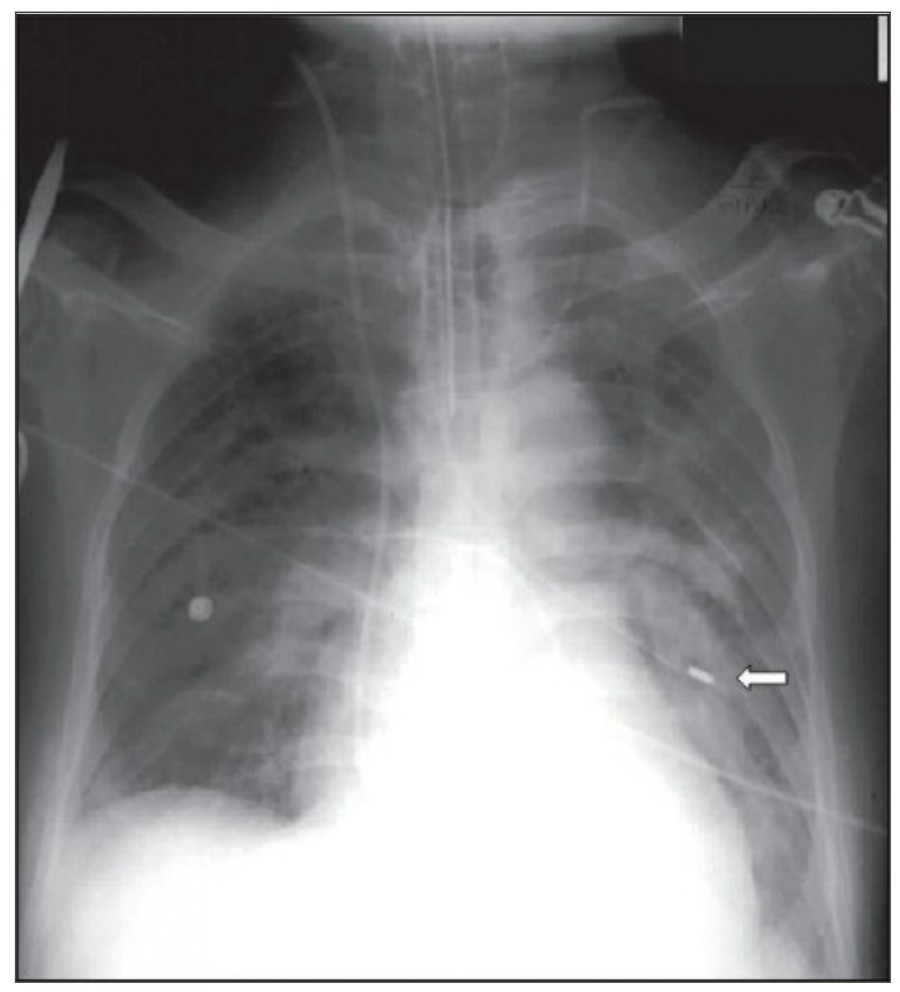

Thoracotomy를 시행받고 나온 환자의 initial postoperative chest X ray에서 각종 line과 endotracheal tube, thoracotomy tube, mediastinal drains, central venous catheter 등을 확인할 수 있을 것이다. 이러한 device들은 그 위치가 제대로 있는지 확인해야 한다.

CABG를 받은 환자에서 lower lobe atelectasis는 흔한데, 주로 왼쪽에 잘 나타나며 수일 내에 별다른 합병증 없이 회복된다. mediastinum도 약간 확대되어 보일 수 있는데, 만약 그 diameter가 많이 증가한다면 mediastinal hemorrhage 등을 시사할 수 있다. CABG 시행 후 약간의 좌측 pleural effusion은 있을 수 있지만 그 양이 많거나 증가한다면 respiratory compromise를 줄이기 위해 intervention이 필요할 수 있다. 따라서 이전의 사진과 비교를 해서 pleural effusion 양의 변화가 있는지 확인이 필요하겠다.

첫 poratable chest X ray 촬영은 각종 line과 device의 위치를 확인하는 데 꼭 필요하며, 위중한 중환자에서 cardiopulmonary disorder를 evaulation 하기 전에 이 device들 위치에 문제가 있지 않은지 확인해야 한다.

Pleural fissure 안에 위치하는 chest tube는 폐 표면이 늘어날 때 종종 배액이 안될 수 있으므로 적절히 기능을 하기 위해서 thoracic cavity 안에 거치되어야 한다. 마지막 side-hole은 radiopaque line의 interruption으로 확인할 수 있는데, 이 지점은 반드시 thoracic cavity 안에 위치해야 한다. Thoracic cavity 밖에 위치하거나 subcutaneous air가 확인되는 경우에 tube가 잘못 들어가 있음을 시사한다. Empyema에서 tube가 제대로 들어가 있지 않다면 배액이 잘 안 되거나 purulent fluid의 loculation이 발생하게 된다.